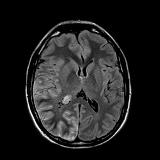

Rationale: Epilepsy is a cause of major morbidity in Sturge Weber syndrome, a segmental vascular neurocutaneous disorder classically associated with facial angiomas, glaucoma, and leptomeningeal capillary-venous type vascular malformations. Seizures occur in more than 75% of affected individuals and are a challenge to treat. The phenomenon of prolonged ictal paresis is a rare seizure sign that can be due to lesions affecting the centro-parietal lobe. Use of steroids to treat leptomeningeal inflammation resulting from angiomatosis of Sturge Weber syndrome has not been reported. Methods: Case Report : A case of a patient with Sturge Weber syndrome presenting with partial seizure like episodes with prolonged post-ictal paralysis, extensive leptomeningeal T2 hyperintensity noted on MRI with good response to Dexamethasone Results: A 24 year male was brought to our hospital after developing persistent left hemiparesis. He had been having brief spells of right sided headache and left hemiparesis for the past 18 months and was on Oxcabazepine for presumed seizure with post-ictal paralysis. He reported recent subtle twitching of the left face and eyes, left hemiparesis and psychomotor slowing with right frontal-temporal headaches but deficits were not resolving like prior episodes. His initial examination showed dysarthria, left homonymous hemianopia, left sided facial weakness, left hemiparesis and left hemianesthesia and although no clinical seizures were noted at this time, Valproic Acid was added for suspected partial status epilepticus and post-ictal paralysis. A 24 hour cEEG showed diffuse right hemispheric slowing, but no ictal activity. MRI brain with contrast showed extensive leptomeningeal FLAIR hyperintensity and enhancement throughout the right cerebral hemisphere consistent with leptomeningeal angiomatosis as well as prominent venous flow voids. Cerebral angiogram showed absence of right hemispheric cortical veins and aberrant venous outflow through multiple pathways, but no AVM or dural AV fistula. After 9 days of persistent deficits, he was started on Dexamethasone 4 mg every 6 hours, which was tapered to 2 mg Q6H with significant improvement in his headaches, left arm strength and communication skills within the next 3 days, and he was discharged with a tapering regimen over 10 days. MRI brain 5 weeks later showed interval decrease in size of previously noted dilated flow voids within the right parietal lobe and collateral draining veins. There was near complete resolution of previously noted leptomeningeal FLAIR hyperintensity. Follow up neurological examination 6 weeks post-discharge showed complete resolution of his neurologic deficits and spells. Conclusions: We report a case of persistent left hemiparesis in a patient with Sturge Weber syndrome attributed to leptomeningeal inflammation of the right cortical hemisphere which showed interval improvement of radiological findings and resolution of neurological deficits with Dexamethasone treatment. Conclusions: We report a case of persistent left hemiparesis in a patient with Sturge Weber syndrome attributed to leptomeningeal inflammation of the right cortical hemisphere which showed interval improvement of radiological findings and resolution of neurological deficits with Dexamethasone treatment. Funding: No funding was received in support of this abstract.